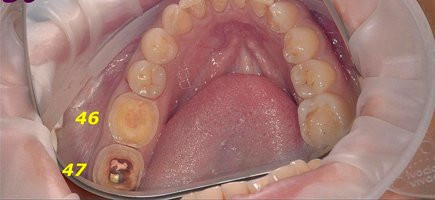

Был составлен план лечения, и в это же посещение мы заменили временную коронку на цифровую коронку из керамики E.max-cad. На данную работу ушло 2 часа. На место отсутствующего 46 зуба планируется

Установка керамической коронки

Специалисты клиники «Доктор Дент» провели реставрацию зубов 3/4 коронками на аппарате CEREC за одно посещение!!! 47 зуб отреставрирован цифровой цельнокерамической коронкой Empress, а 46 зуб — упроченной цифровой цельнокерамической

Доктор: Смирнова Людмила Игоревна